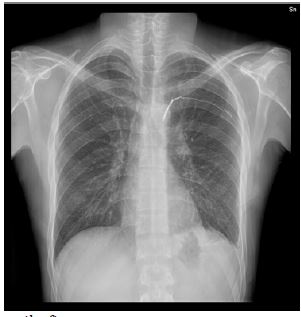

Clinical examination revealed two penetrating wounds in subscapular region bilaterally (approximately 1,5 cm each). A chest X-ray and chest CT were performed; radiological exams demonstrated bilateral pneumothorax and no active pleural effusion. Two chest tubes were immediately placed, one on each side, with active air leakage and sudden improvement of dyspnea. The patient was stabilized; a chest X-ray showed resolution of the bilateral pneumothorax and hemothorax. After 3 days of observation the pleural drainage were removed and the patient finally discharged for follow-up. One week later, the patient returned to the ER complaining of acute chest pain and dyspnea.

A new chest X-ray showed left hemothorax. Subsequently, a chest CT with contrast was performed, revealing the presence of an intercostal pseudoaneurysm in the fifth intercostal artery, with signs of active bleeding.

The patient was discharged in good general condition; chest X-ray performed one month after surgery did not disclose any pathologic finding (Figure 3).